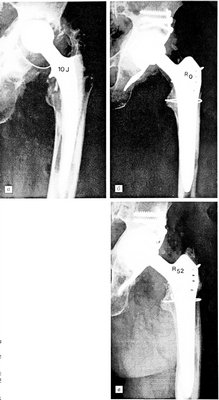

Рис. 1.

а — через 10 лет после первичного тотального эндопротезирования тазобедренного сустава цементируемой конструкцией: высокая степень деструкции костной ткани с вывихом головки (Engelbrecht 4);

б — непосредственно после реконструкции с использованием ацетабулярной опорной чашки Schneider и пластики спонгиозой;

в — через 52 мес после тотальной реконструкции.